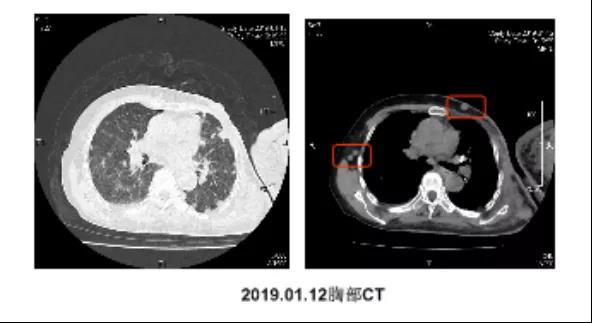

一个人生病时,回想这一生,什么对他来说最重要呢? 2020年,是马先生抗争病魔的第5个年头。 “我老公是15年12月份...